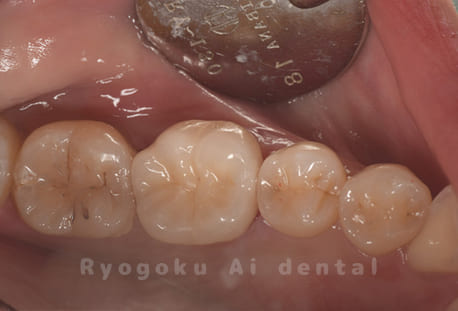

Case08

-

- 原因

- 虫歯

- 治療内容

- セラミックインレー

- 治療費用

- 77,000円

奥歯の黒い点が気になるということで来院された患者さんです。白い詰め物を外したところ、虫歯が中で大きく広がっていたため、患者さんと相談し、セラミックインレーで治療を行いました。

<リスク・副作用>

過度の咬合や衝撃で割れることがあります。